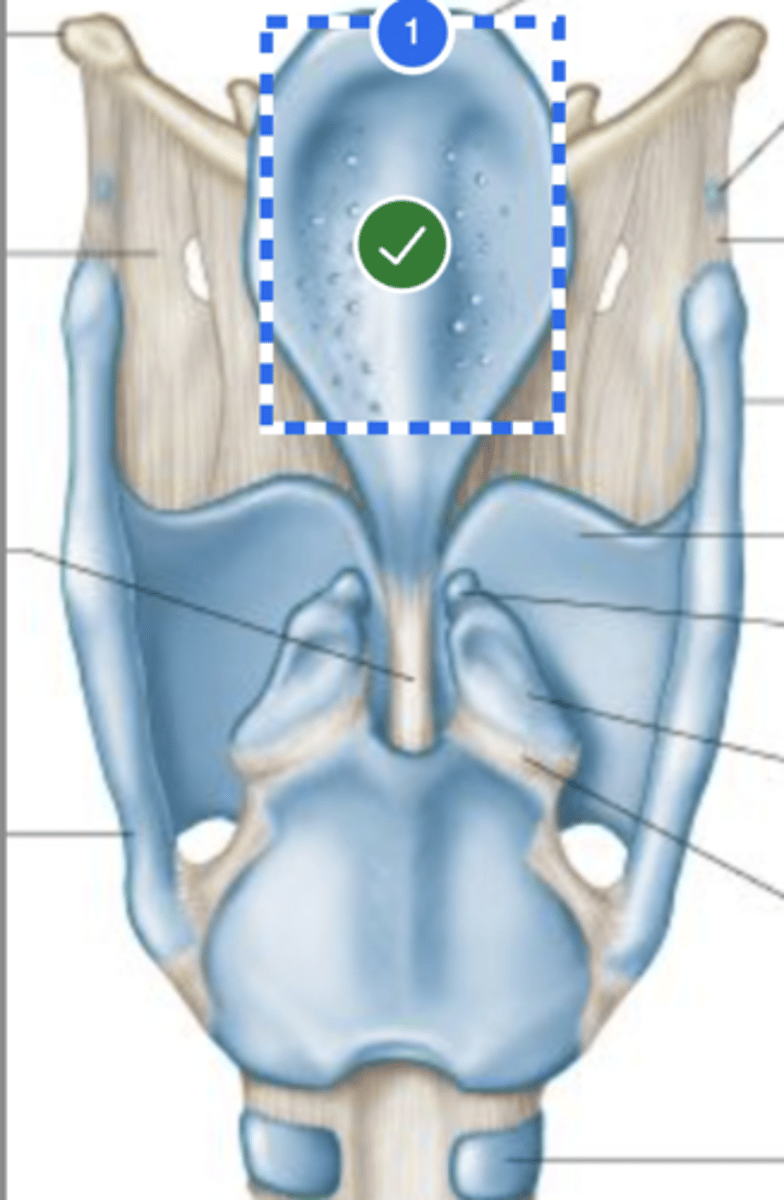

Label hyoid bone (anterior view)

Label epiglottis (anterior view)

Label Thyroid cartilage (anterior view)

Label cricoid cartilage (anterior view)

Label 2nd tracheal ring (anterior view)

Label left cricothyroid joint (anterior view)

Label Cricoid cartilage (posterior view)

Label Right arytenoid (posterior view)

Label Left cricothyroid joint (posterior view)

Label Laryngeal surface of epiglottis (posterior view)

Label 1st tracheal ring (posterior view)